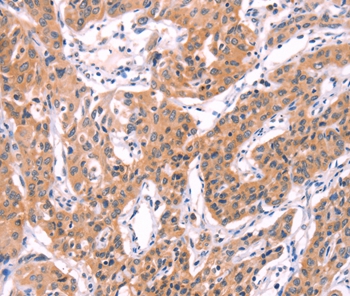

Immunohistochemical analysis of paraffin-embedded Human lung cancer tissue using #35991 at dilution 1/40.

Immunohistochemistry: 1:50-1:200